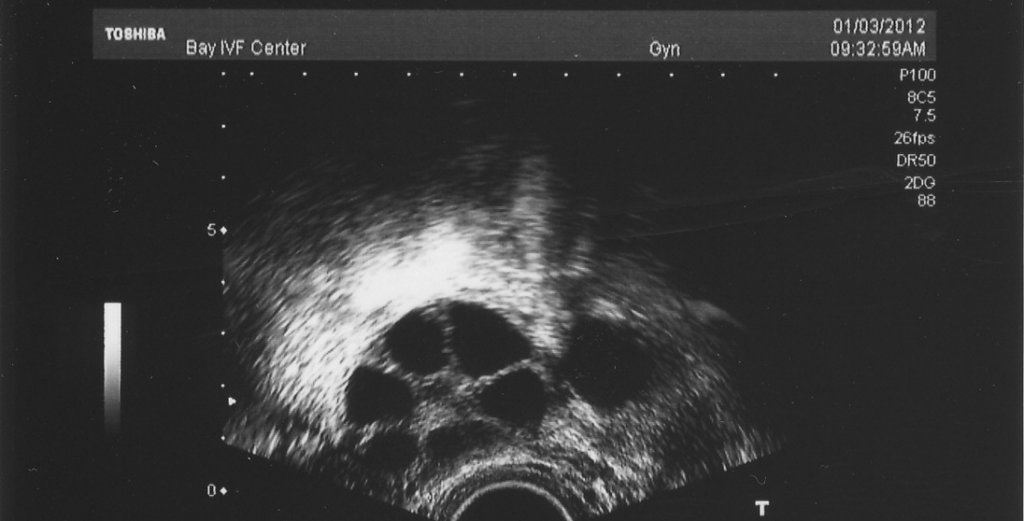

Estradiol thickens your endometrium so it’s nice and cushy for an embryo. Doctors aim for at least 7-8 mm of thickness—think of it like fluffing a pillow before a guest arrives.

- ✔️ Tip: Ask your doctor for an ultrasound to check your lining. If it’s too thin, they might up your estradiol dose.